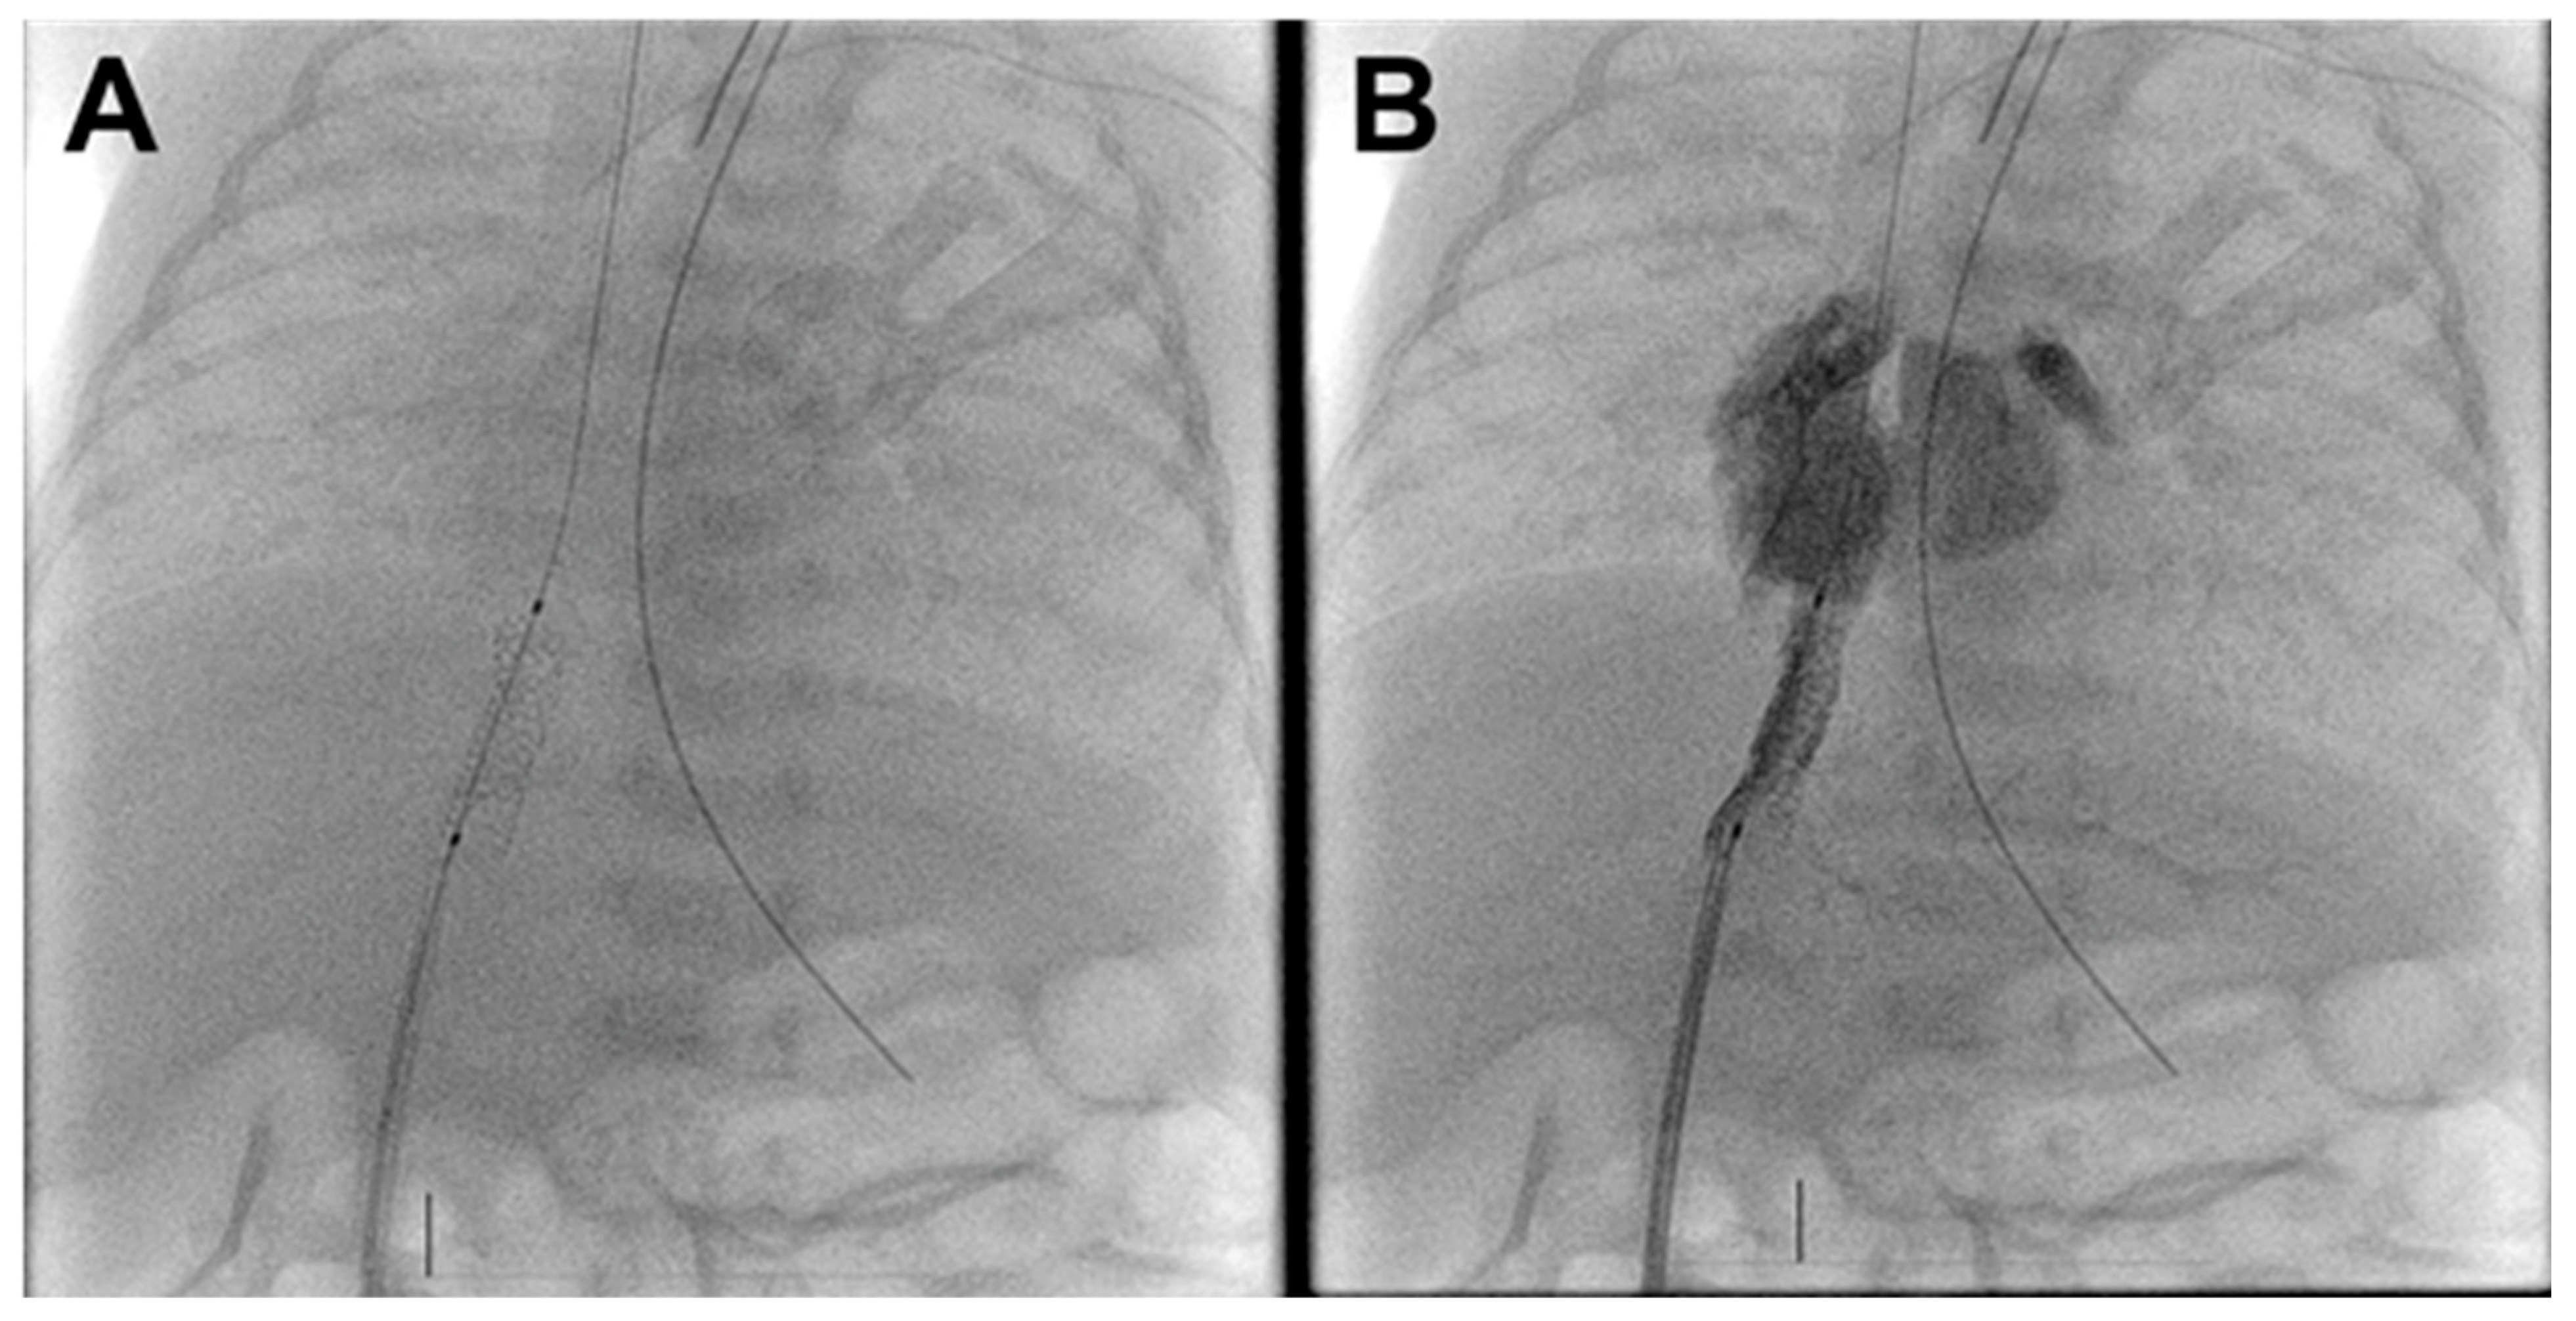

A 15 × 4 mm Onyx drug-eluting stent (Medtronic Inc., Santa Rosa, CA, USA) was used for intervention. This stent was selected due to its low-profile delivery system, fair radial strength, and drug-eluting properties to potentially reduce the risk of in-stent restenosis. The stent was easily deployed in the DV (Fig. 2A). Post deployment angiography showed improved flow through the TAPVR with no residual DV stenosis (Fig. 2B, Supplemental Video S1).

The infant’s lung compliance and oxygenation improved immediately. Preprocedural blood gas was 7.43/48/104 with SpO2 96% on 43% FiO2. Post procedural blood gas was 7.54/34/110 with SpO2 97% on FiO2 28%. A final PA injection showed no residual stenosis. Given improvement in respiratory status and angiographic evidence of relief of obstruction, the decision was made to end the case. Total contrast 10.8 mL/kg. Fluoroscopy time 11 min. Radiation dose 11 mGy.

Figure 2: Post-intervention fluoroscopy and angiogram. (A). Well-positioned ductus venosus stent. (B). Umbilical vein injection demonstrates unobstructed ductus venosus flow to the right atrium with limited portal venous filling.